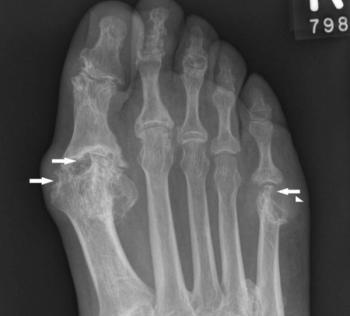

Can you spot the x-ray evidence to detect the suspected diagnosis?

Clinical presentation, history, and laboratory evaluation can make a diagnosis of gout, but crystal examination is the “gold standard.”

Elevated serum uric acid level is pathognomonic for gout. Untreated gout may lead to tophi, nephropathy, and uric acid nephrolithiasis.